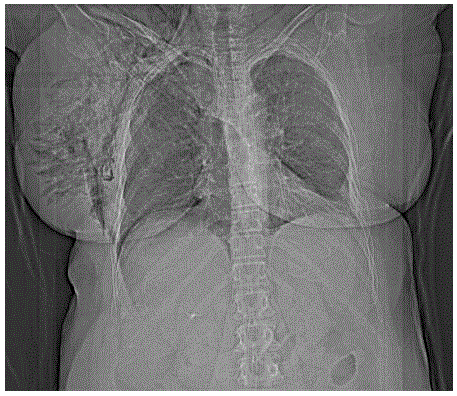

Mulher de 64 anos, vítima de atropelamento, dá entrada no serviço de emergência transportada pela equipe de resgate. Refere dor torácica do lado direito. Apresenta frequência respiratória: 25 ipm, Sat. O2: 90%; frequência cardíaca: 120 bpm; pressão arterial: 140x90 mmHg; Glasgow coma escore: 15. Ao exame clínico murmúrio vesicular diminuído do lado direito, mama direita 3x o tamanho da mama esquerda, enfisema de subcutâneo no hemitórax direito. O raio-X de tórax mostra:

enunciado 1542984-1

O tratamento mais adequado neste momento é: